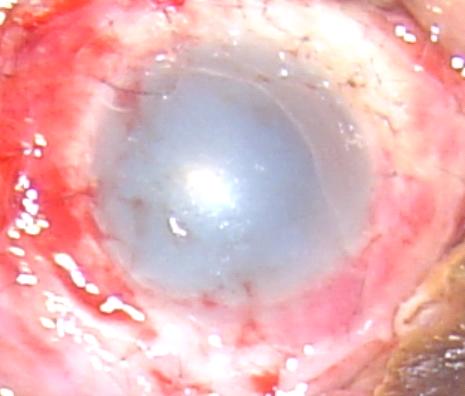

10天前收了一个双眼碱烧伤的病人,很重,所有的角结膜缘组织均苍白坏死。同时伴有面部浅2度――3度烧伤。给予切除坏死组织,冲洗,前房穿刺等急诊处理后病人的水肿略微减轻,视力FC/50CM,入院后给予血清、枸橼酸钠、VC、肝素、激素(头7天)、EDTA、贝复舒等点眼后不见好转,上皮细胞无。决定近期给予羊膜移植加异体干细胞移植(他弟的)。

右眼 右眼